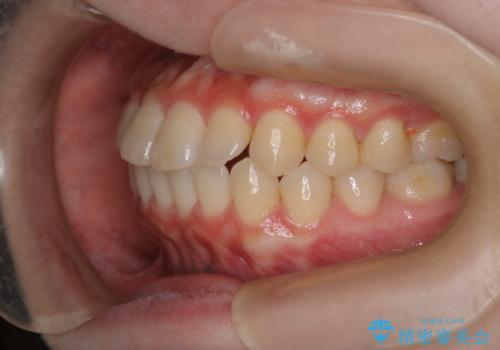

前歯と奥歯のガタガタを矯正で改善

- 患者様は、前歯と奥歯のガタガタ(叢生)を改善し、正面から見た時の歯並びを美しく整えたいとのご要望で来院されました。診断の結果、非抜歯での矯正が可能と判断し、インビザラインを使用する治療計画を立案しました。透明な矯正装置で目立ちにくい治療を行いながら、前歯と奥歯の両方を整列させることを目標にしました。

インビザラインを用いて、前歯の見た目を重視しつつ、奥歯のガタガタも改善しました。特に正面から見た際の美しい歯列を意識し、段階的に歯を移動させることで、全体の調和を図りました。治療中は、適切な装着時間を守ることや、装置の清潔を保つことが重要でした。また、歯肉や歯列全体に無理な負担がかからないように移動を管理しながら治療を進めました。結果として、前歯と奥歯がきれいに並び、見た目にも機能的にも満足いただける仕上がりとなりました。